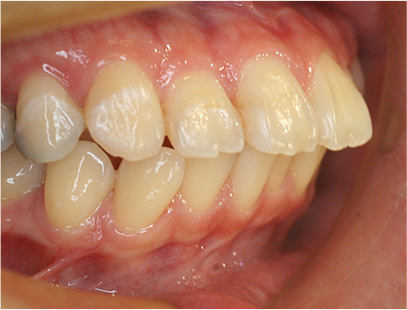

症例03

前歯が出ている症例

上の歯が出いることを主訴として来院されました。

通常通り検査を行い、「上下顎前突」と診断されました。

治療計画

上下4番目の歯を抜歯してそのスペースを利用して上の前歯を内側に移動させる事としました。

矯正の種類

上は裏側矯正

下は表側からの白い矯正装置(セラミック)

治療前

• 矯正治療前の横顔

• 正面

• 上側

• 下側

• 左側

• 右側